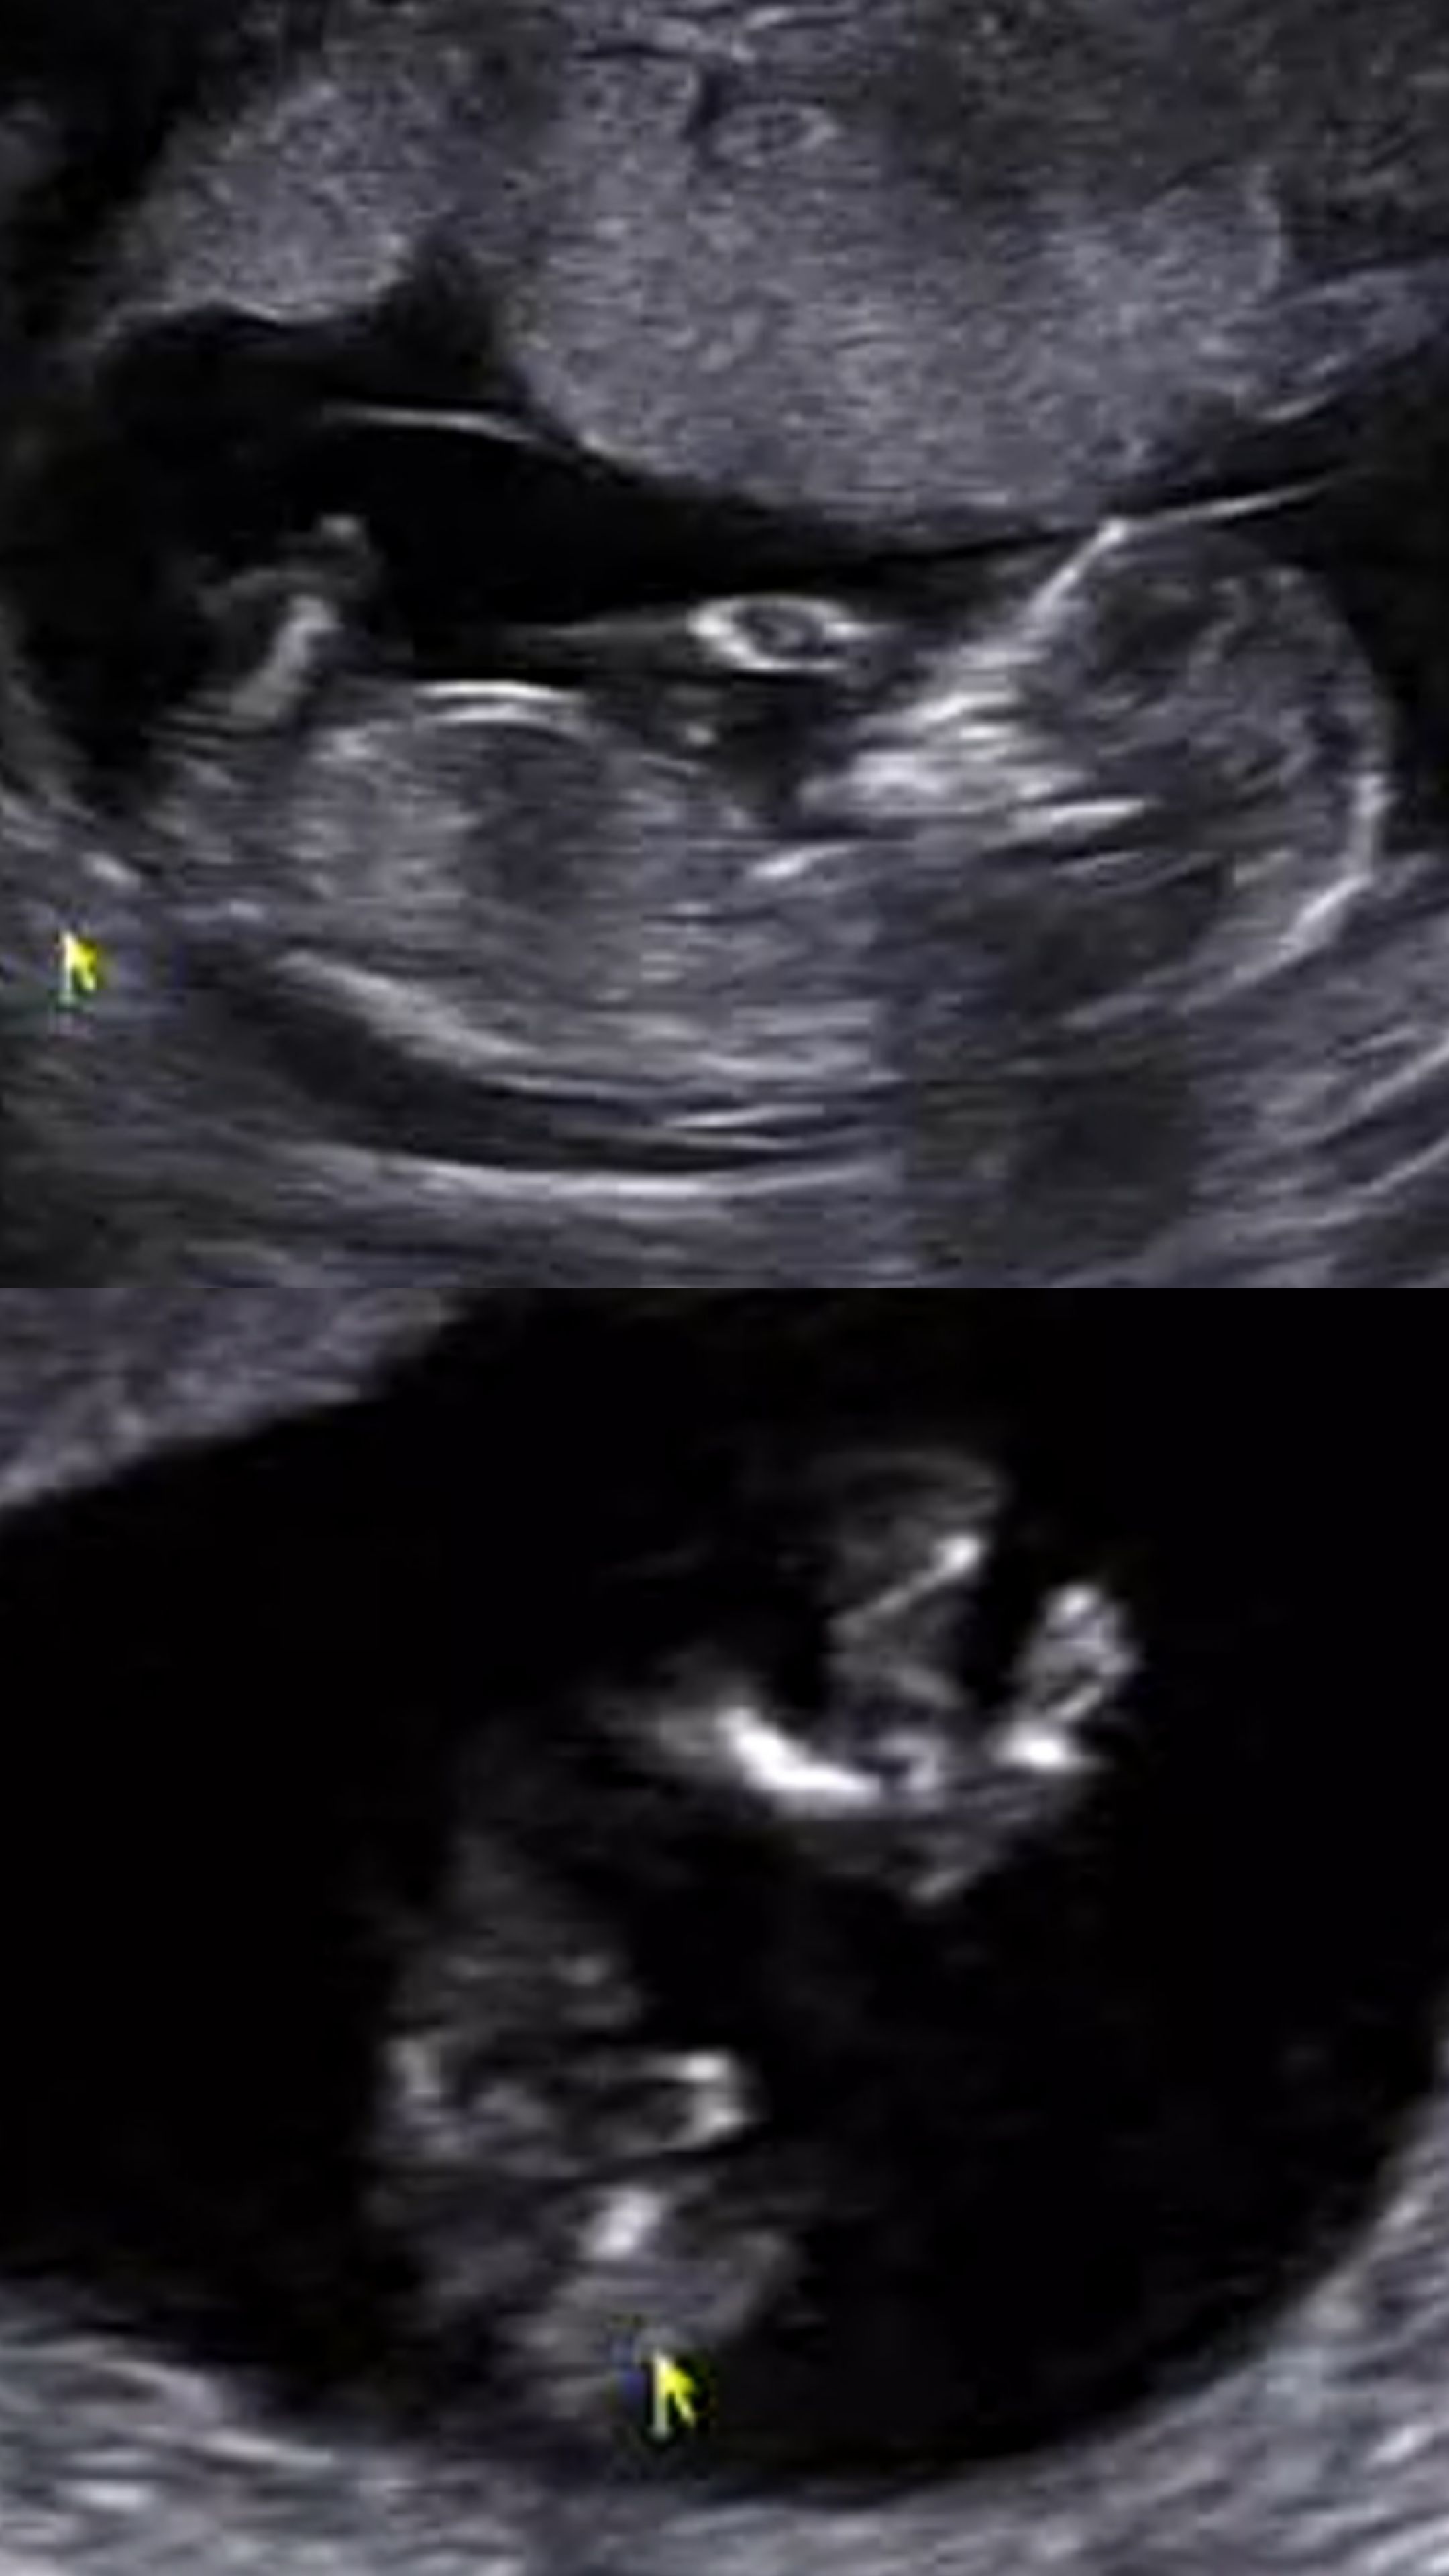

오늘 13주1일 입체초음파 처음봤는데 엄청 신기하더라구요! 초음파 보는 5분이 훌쩍 갔어요ㅎㅎ 우리 아가는 딸일까요 아들일까요?? 각도법으로는 딸이라고 나오는데 적극적인 참견부탁드려요ㅎㅎ

거기가 잘 안보여요 그나마 보이는 3번째 사진만 봐서는 애매해요